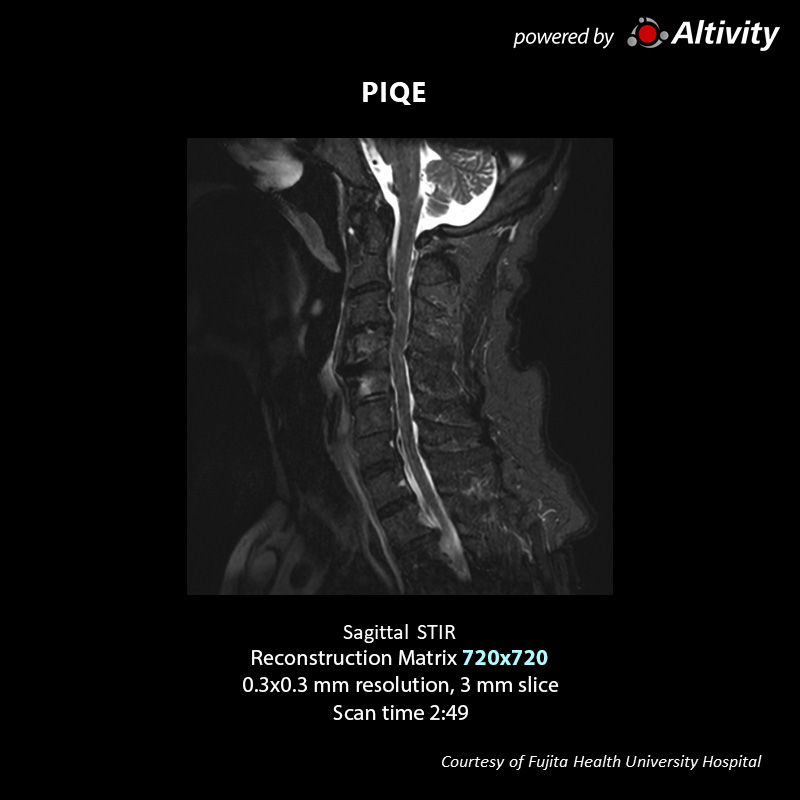

Neuro & Spine

Vantage Galan 3T

Sagittal T2w for c spin

The original image is a 288 matrix with a 3 mm slice thickness and relatively low resolution, resulting in high SNR.

PIQE reconstruction can acquire high quality images within acceptable scan times.